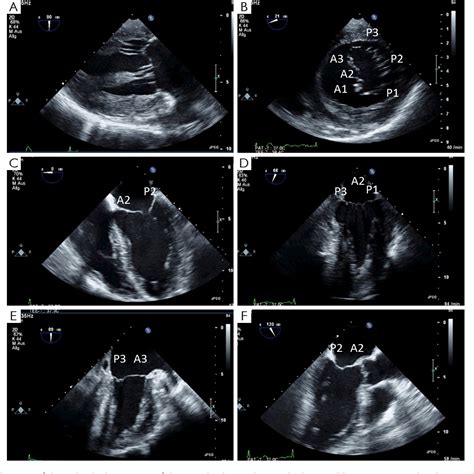

A Transesophageal Echocardiogram (TEE) is a diagnostic test that uses high-frequency sound waves (ultrasound) to create moving images of your heart. By positioning the transducer—a device that emits sound waves—in the esophagus, doctors can bypass the interference caused by chest tissue and bones. This diagnostic tool is considered the "gold standard" for visualizing specific cardiac structures, such as the heart valves, the left atrial appendage, and the aorta, with superior precision compared to external imaging.

• Evaluating the severity of valvular heart disease.

• Detecting infections of the heart valves (endocarditis).

• Assessing structural heart defects, such as an atrial septal defect.